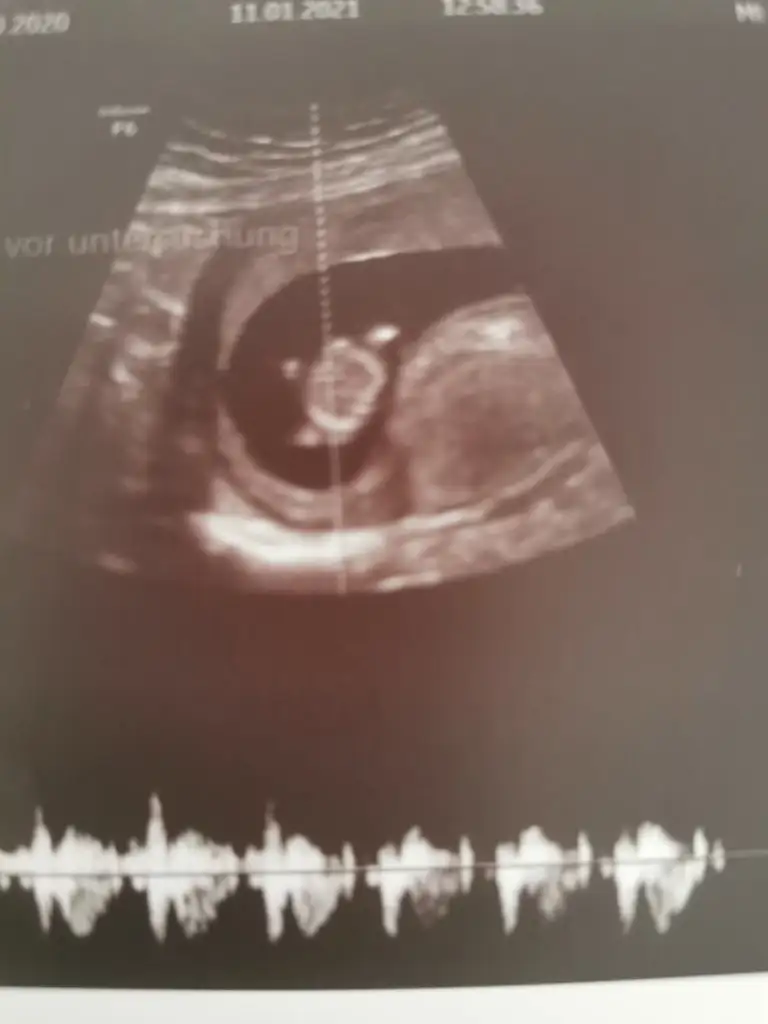

Anket Nub teorosi dogru tahminmi arkadaşlar

Nu teorisi dogrumu yanlışmı

• Tahminim dogrumu

OY: 357 76,6%

• Tahminim yanlışmı

OY: 109 23,4%

• Ankete Katılan

466

Nub teirosi doğru çıktı bir kız yeğenim olacak🥰 teşekkürler 🥰